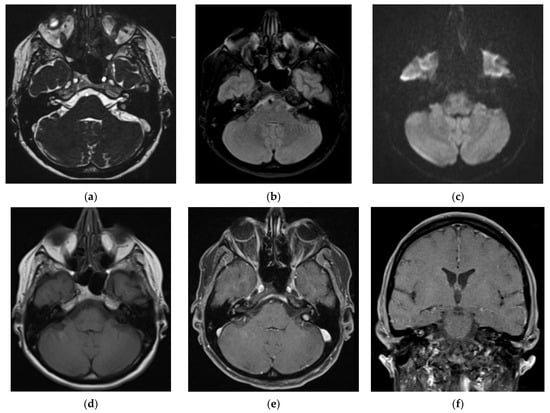

3.1. CASE 1

3.2. CASE 2